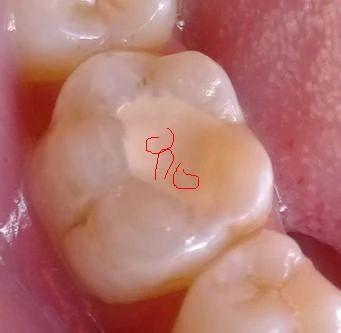

3、牙齿遇到外来刺激(温度、机械、化学刺激)时产生的酸痛感觉,一般人叫“倒牙”,医学上称牙本质过敏症,与牙本质暴露有关。

1、造成牙本质暴露的原因很多,最常见的是牙齿过度磨损。龋病侵犯到牙本质时也会产生酸痛。但不是所有的牙本质暴露部位都会产生酸痛,牙酸的发生还与牙本质内细小管道与牙髓神经末梢的敏感性或传导性有关。